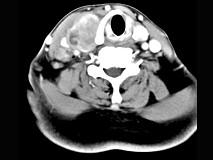

问题 女性,54岁,右侧颈部肿大近1年,近来病人有声嘶、吞咽困难,CT扫描如图,请选择正确的描述和答案()

选项 A.右侧甲状腺肿大,密度减低 B.增强扫描示甲状腺呈不规则强化团块影,其内有低密度区,病灶境界不清 C.右侧颈内静脉增粗,其内可见不规则充盈缺损区 D.考虑甲状腺癌 E.右侧颈内静脉瘤栓形成

答案 ABCDE